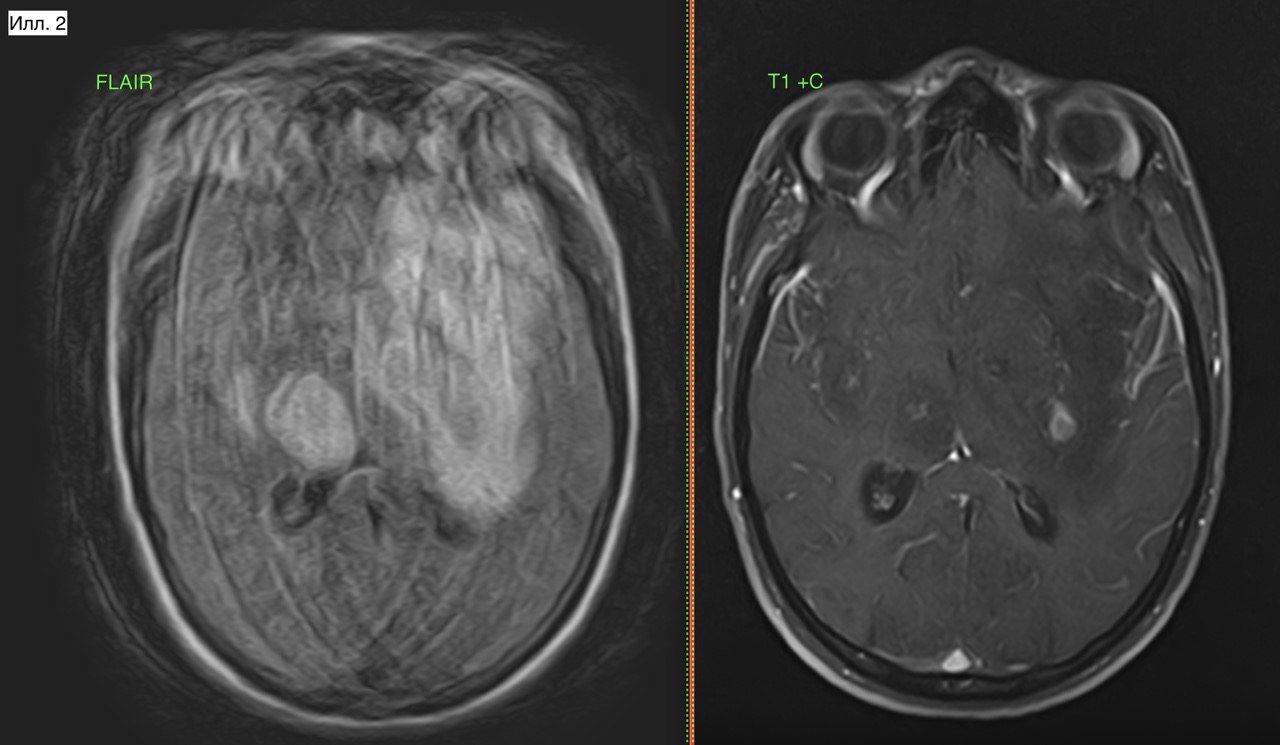

Пациент Ф., 18 лет. Пациент проходил обследование по направлению медкомиссии военкомата. Находка случайная, в анамнезе есть (вроде бы) ЧМТ. На илл. 1-2 хорошо определяется зона измененной структуры вещества мозга с увеличением объема пораженного участка. С учетом клинической картины (т.е. отсутствие каких-либо симптомов) заключение без дифференциального диагноза - опухолевое поражение. По картине это может походить на энцефалит, но напомню об отсутствии клинических знаков. Последствием ЧМТ это не может быть никак. В этой связи скиалогическая запись в заключении (илл. 3) не корректна, как вариант - использовать дифференциальный ряд и рекомендовать в/в контраст.

Илл. 2. Хорошо видна не только потеря границы коры мозга (стрелки), но и деформация извилин с сужением борозд.